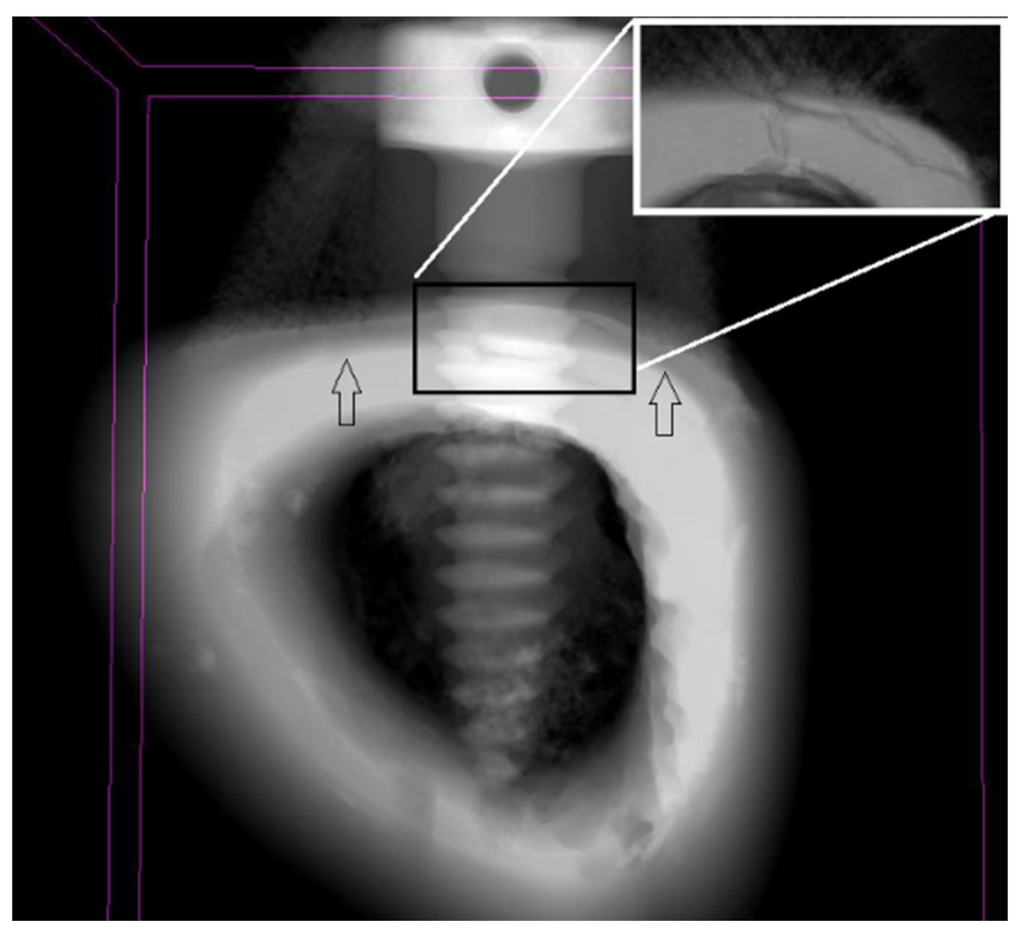

Figure 6. Micro-CT scan of the temporary screws attached to rabbit’s tibia after 1 week. Cortical and cancellous bone limits are identified by arrows. Detail of fractured bone due high stress induced during mini-implant insertion at increasing magnification.

Reckoning the constant values presented above and Equation 4, we find the insertion strength 𝜏 = 1.01 MPa. Insertion strength provides an indication of the stress on bone tissue, mainly cortical shell. Knowing the insertion strength, it is possibly to avoid bone fracture during screw placement. Despite the values of insertion torque measured in Table 1 were in accordance with the baseline disclosed in literature for adequate success rate of biomedical temporary screws, the importance of these calculations lies in the ability of the surgeon to select the correct diameter of screws in order to avoid cortical fracture during attachment [20,21]. From our calculations, for 1.5 mm screw diameter, the stress that bone can stand is close to the value transmitted during screw placement. The correlation coefficient between insertion strength and torque was just 1.01. This means that for the conditions of our experiment, cortical density strength is slightly higher than insertion torque brought forth during screw placement. Although these calculations were performed in synthetic foam, it is consistent with our results from in vivo tibia of rabbits, where an example of cortical failure was identified on the outer region of the tibia (Figure 6). In order to prevent cortical fracture, surgeons ought to choose an adequate design, length and diameter pf the screw according to bone quality, insertion technique (with or without use of 1.0 mm drill before insertion) and angle of penetration [13,17,19,22,23,24,25,26,27].